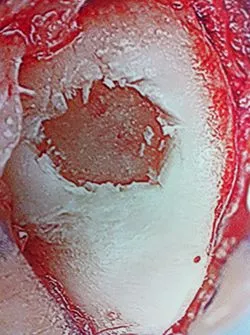

Osteochondral Autograft Transfer System (O.A.T.S.)

The following pictures are debridement of damaged cartilage that is abnormal in appearance and/or loose. This is removed completely to expose the subchondral (underneath cartilage) bone plate.

Drill holes are then placed through the bone plate to allow bleeding in the area, which will aide in healing of the cartilage surface with fibrocartilage, which is a kind of scarring of cartilage.